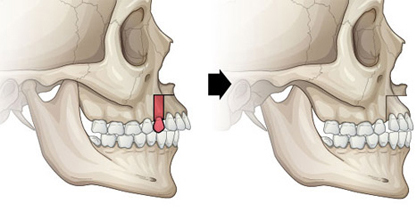

一般的外突嘴手术在医学上叫做上颌前部截骨术(ASO, anterior segmental osteotomy),是指将包括牙床在内的骨骼切断之后向后移动的方法。